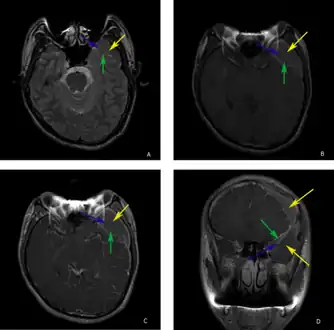

a-d)individual with complicated arachnoid cyst

The diagnostic process typically begins with a medical history workup followed by a medical examination by a physician. Imaging tests, such as CT scans and MRIs, help provide a clearer picture. The physician typically looks for fluid (or other bodily substance) filled sacs to appear in the scans, as is shown in the CT scan of a colloid cyst. A primary health care provider will refer an individual to a neurologist or neurosurgeon for further examination. Other diagnostic methods include radiological examinations and macroscopic examinations. After a diagnosis has been made, immunohistochemistry may be used to differentiate between epithelial cysts and arachnoid cysts.[2] These examinations are useful to get a general idea of possible treatment options, but can be unsatisfactory to diagnose CNS cysts.[3][5] Professionals still do not fully understand how cysts form; however, analyzing the walls of different cyst types, using electron microscopes and light microscopes, has proven to be the best diagnostic tool. This has led to more accurate cyst classification and correct course of action for treatments that are cyst specific. In the past, before imaging scans or tests were available, medical professionals could only diagnose cysts via exploratory surgery.[2]